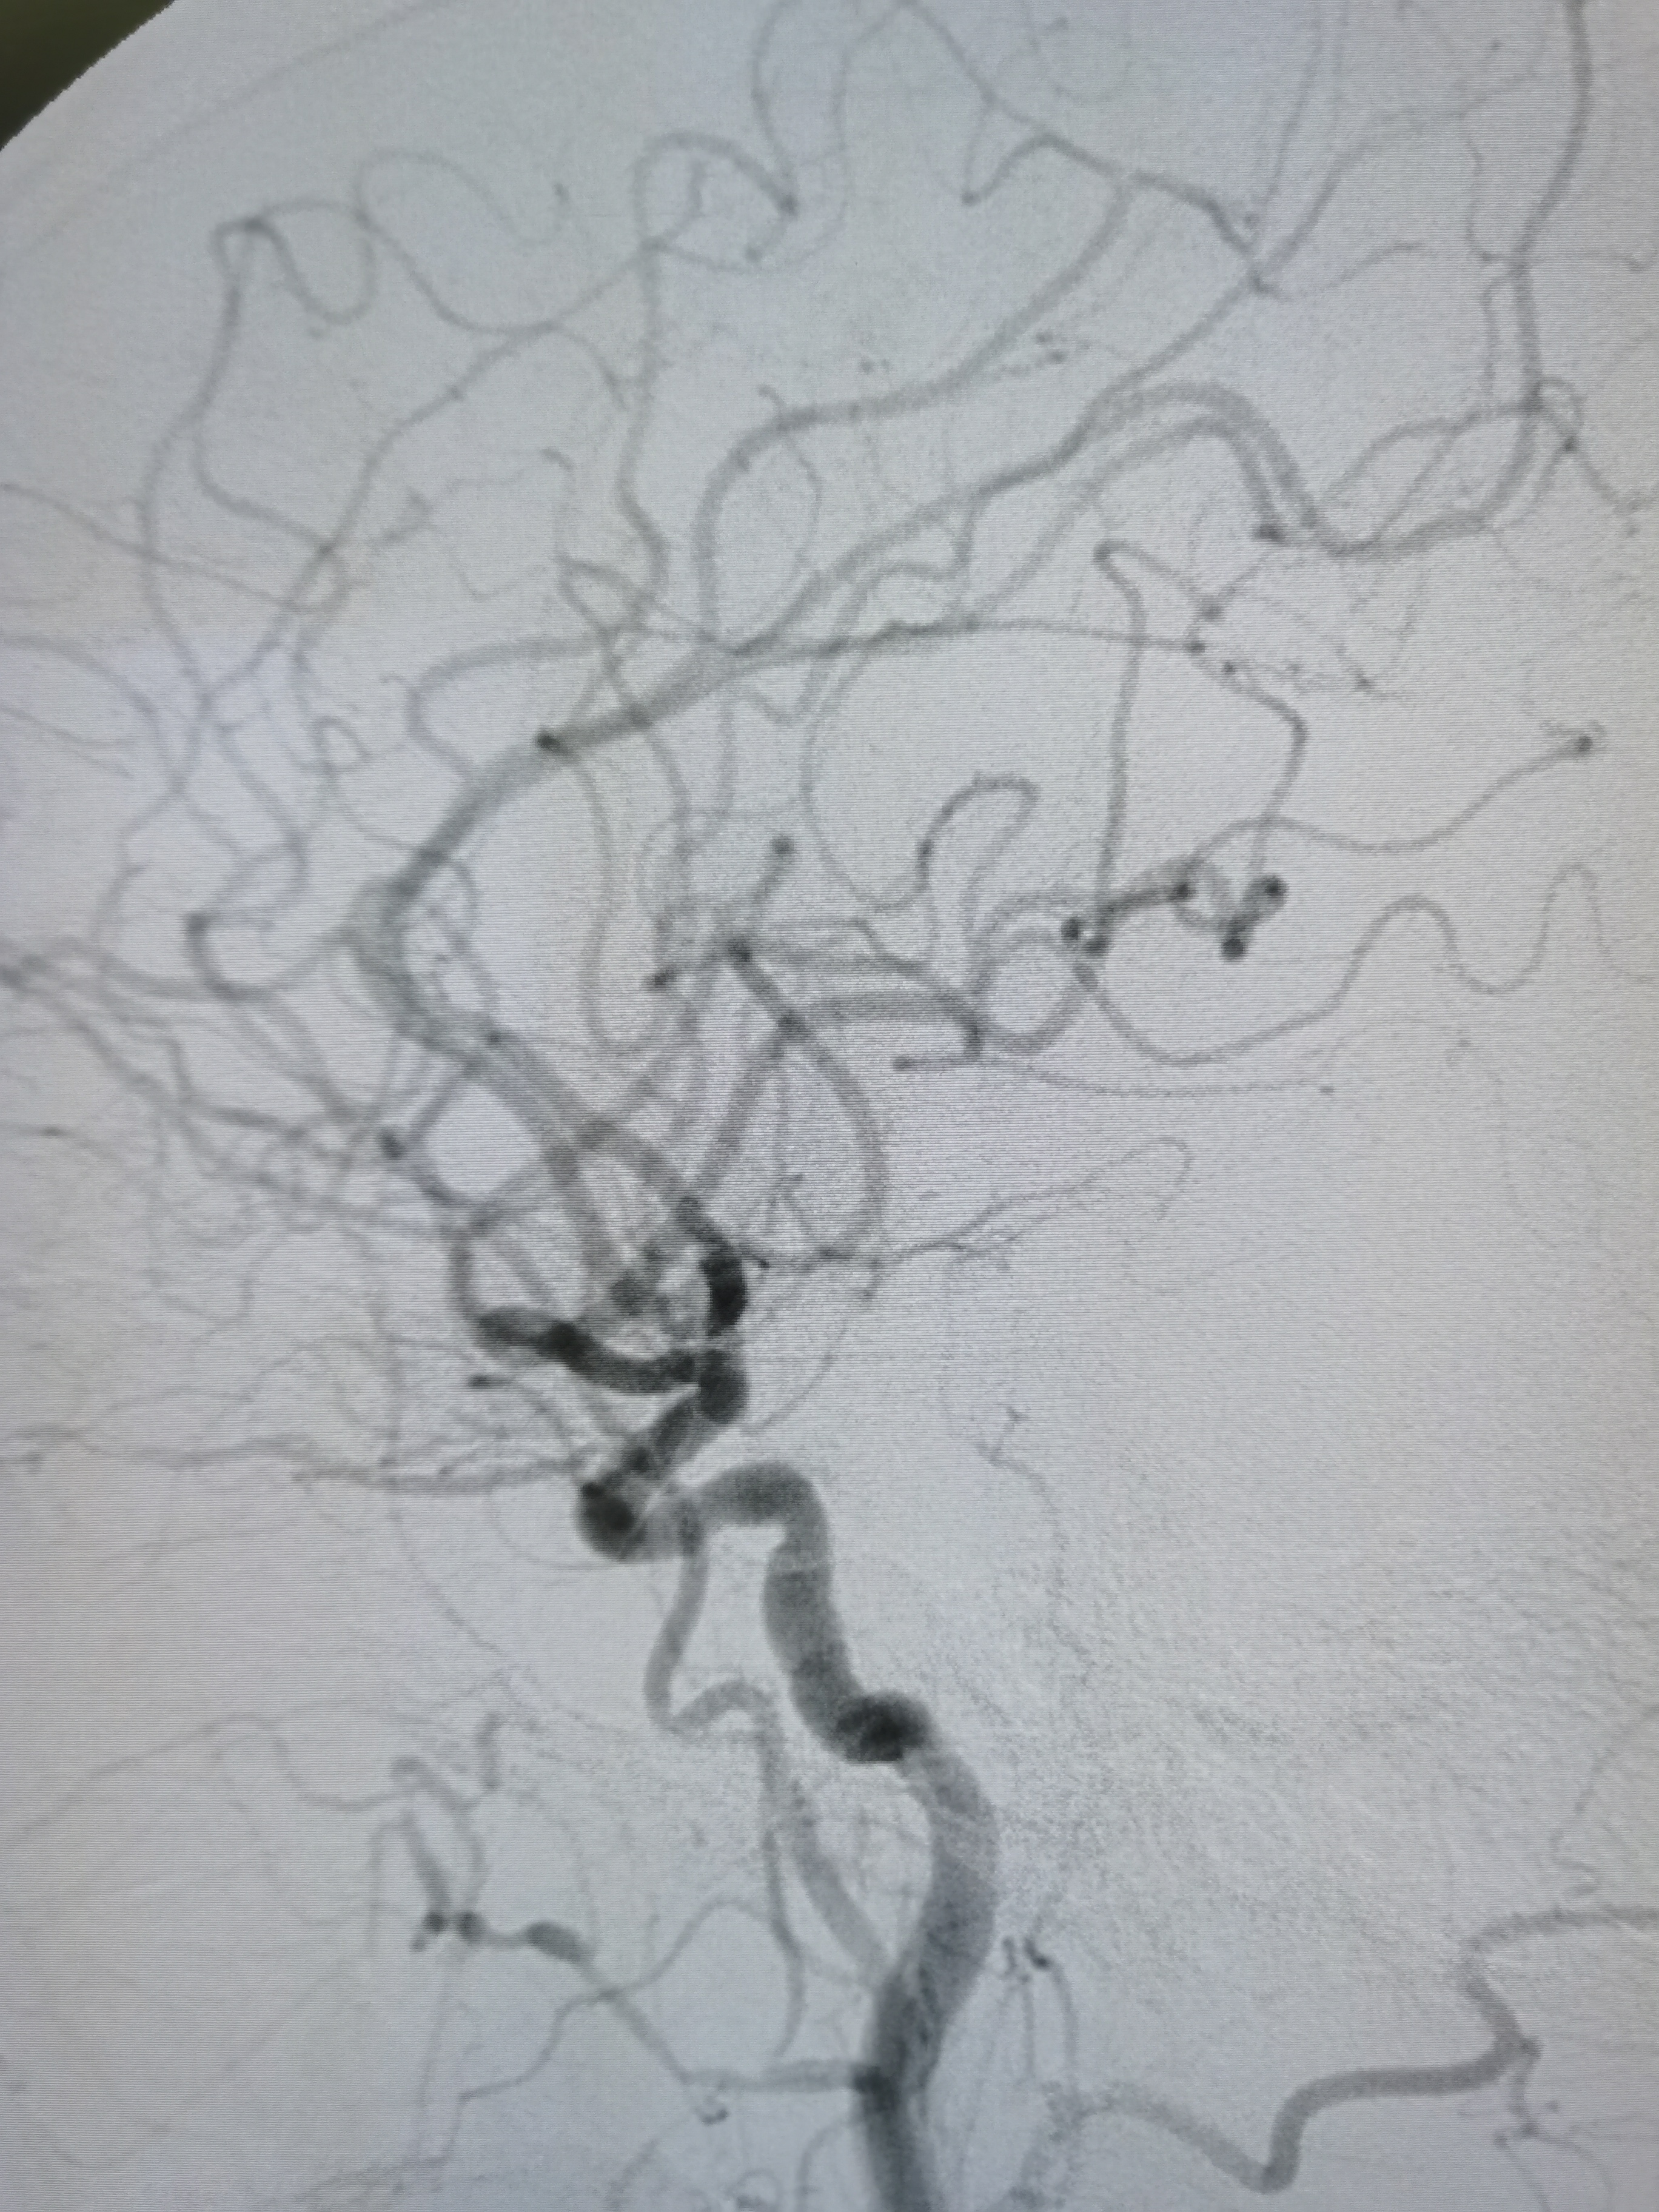

左侧锁骨下动脉硬化,左椎优势。

基底动脉正常。

右椎动脉劣势。

颅内段显影可。

支架释放后颅内血供良好。

颅内血供良好。

术后患者无不适主诉,积极控制血压,避免高灌注损伤。